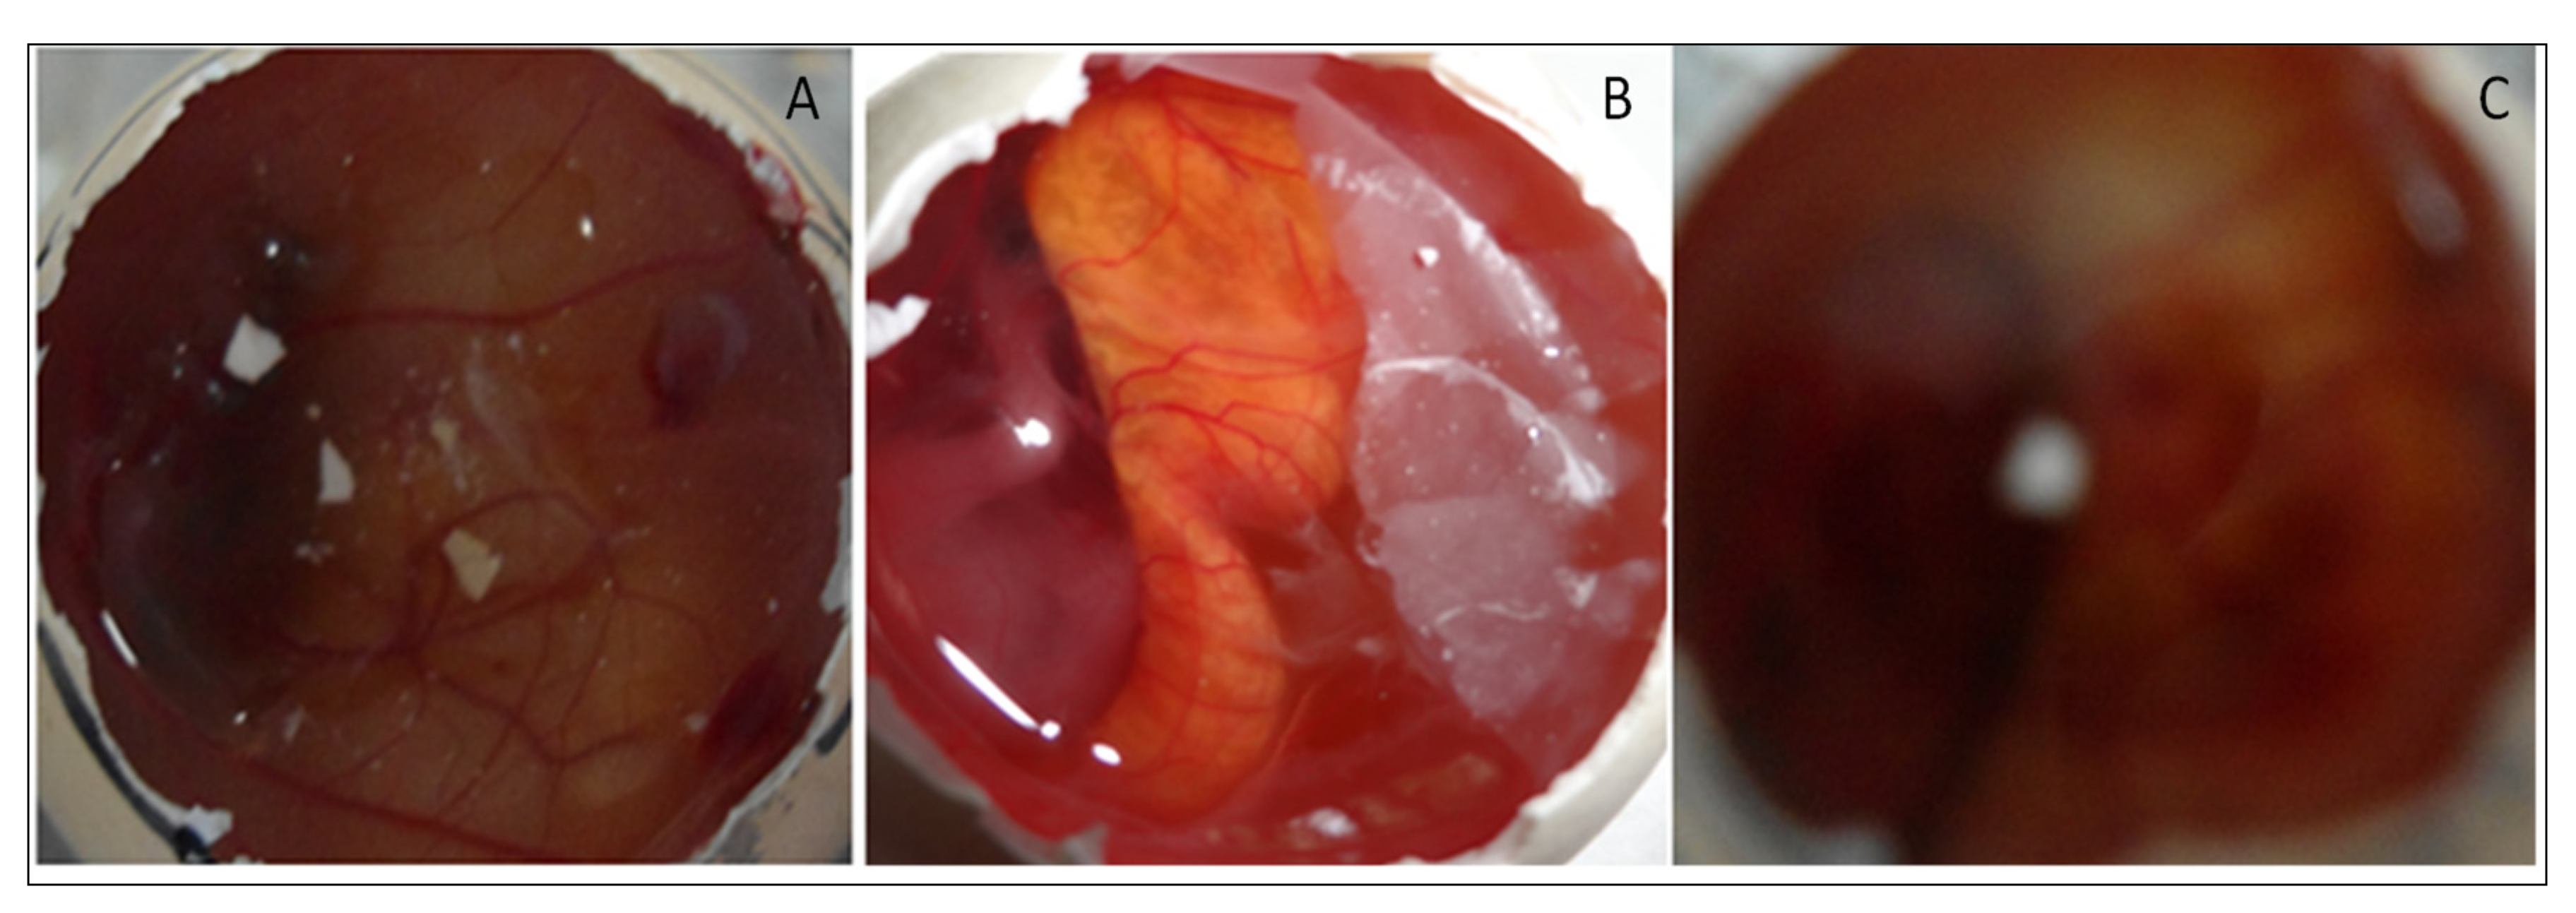

4.8.8. HET CAM Irritation Study

HET-CAM (irritation) study was performed for EM-NLCs-opt-IG4, normal saline (0.9% NaCl, negative control) and positive control 0.1N sodium hydroxide) using a fertilized hen egg’s (Figure 8). The developed CAM after incubation is similar to the artery and vein of an eye. EM-NLCs-opt-IG4 and normal saline-treated CAM showed no irritation. There was no haemorrhage and bleeding from the artery and vein of CAM (no breaking) observed in 5 min. and the score was found to be closer to zero. In addition, the positive control (0.1N NaOH) treated CAM depicted a score of 6 and indicated haemorrhage of artery and vein of CAM in 5 min. So, the positive control treated CAM is considered a severe irritant. The study revealed that the developed EM-NLCs-opt-IG4 formulation was found to be non-irritant and safe for ophthalmic administration.

Figure 8.

HET-CAM image of (A). EM-NLCs-opt-IG4, (B). Negative control (0.9% NaCl) and (C). Positive control (0.1 N NaOH).